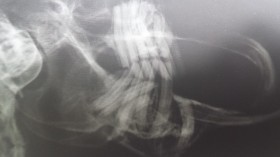

Dentalröntgen

Füllung des Oberkieferfangzahn bei einer Katzeretrogrades Zahnwachstum bei einem Kaninchen